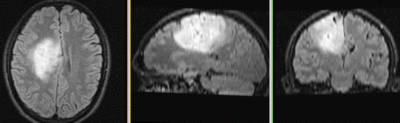

Registration Results

RegLib C27 Result1.gif original and registered pair of FLAIR and DTI (click to enlarge)

RegLib C27 Result2.gif original and registered pair of T1 and DTI (click to enlarge)